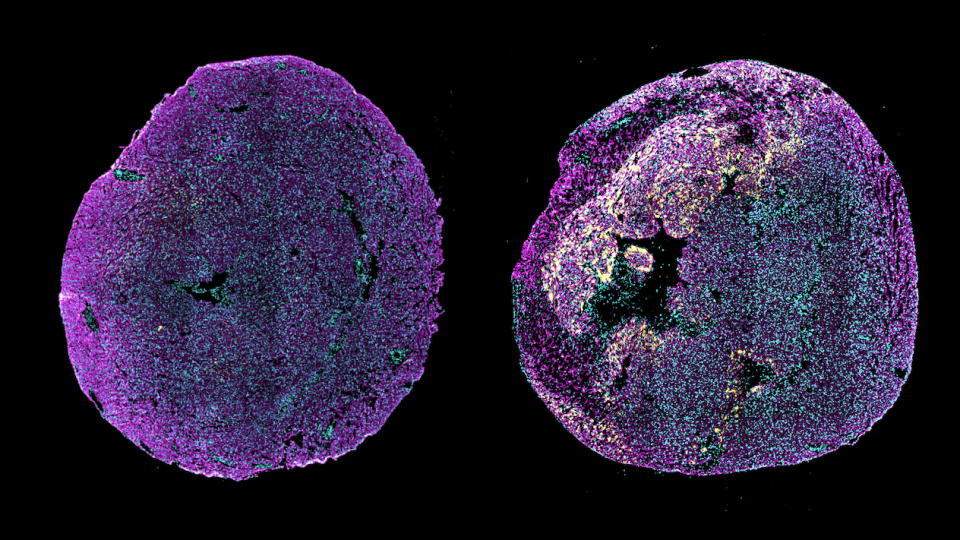

Injecting the saRNA-LNPs into the muscles of mice boosted production of pro-ANP in the treated muscle tissue. Some pro-ANP production was also seen in lymph nodes, but not in other organs. This lasted for at least four weeks. The pro-ANP produced in muscles moved into the blood and traveled to the heart, where it was converted into ANP.

The researchers next tested a single injection of saRNA-LNPs immediately after a heart attack in a mouse model. Treated mice had significantly improved heart function 28 days later compared to untreated mice. They also had less dead heart tissue and reduced scarring. Giving the treatment a week after the heart attack had similar beneficial effects but wasn’t as effective as immediate treatment.